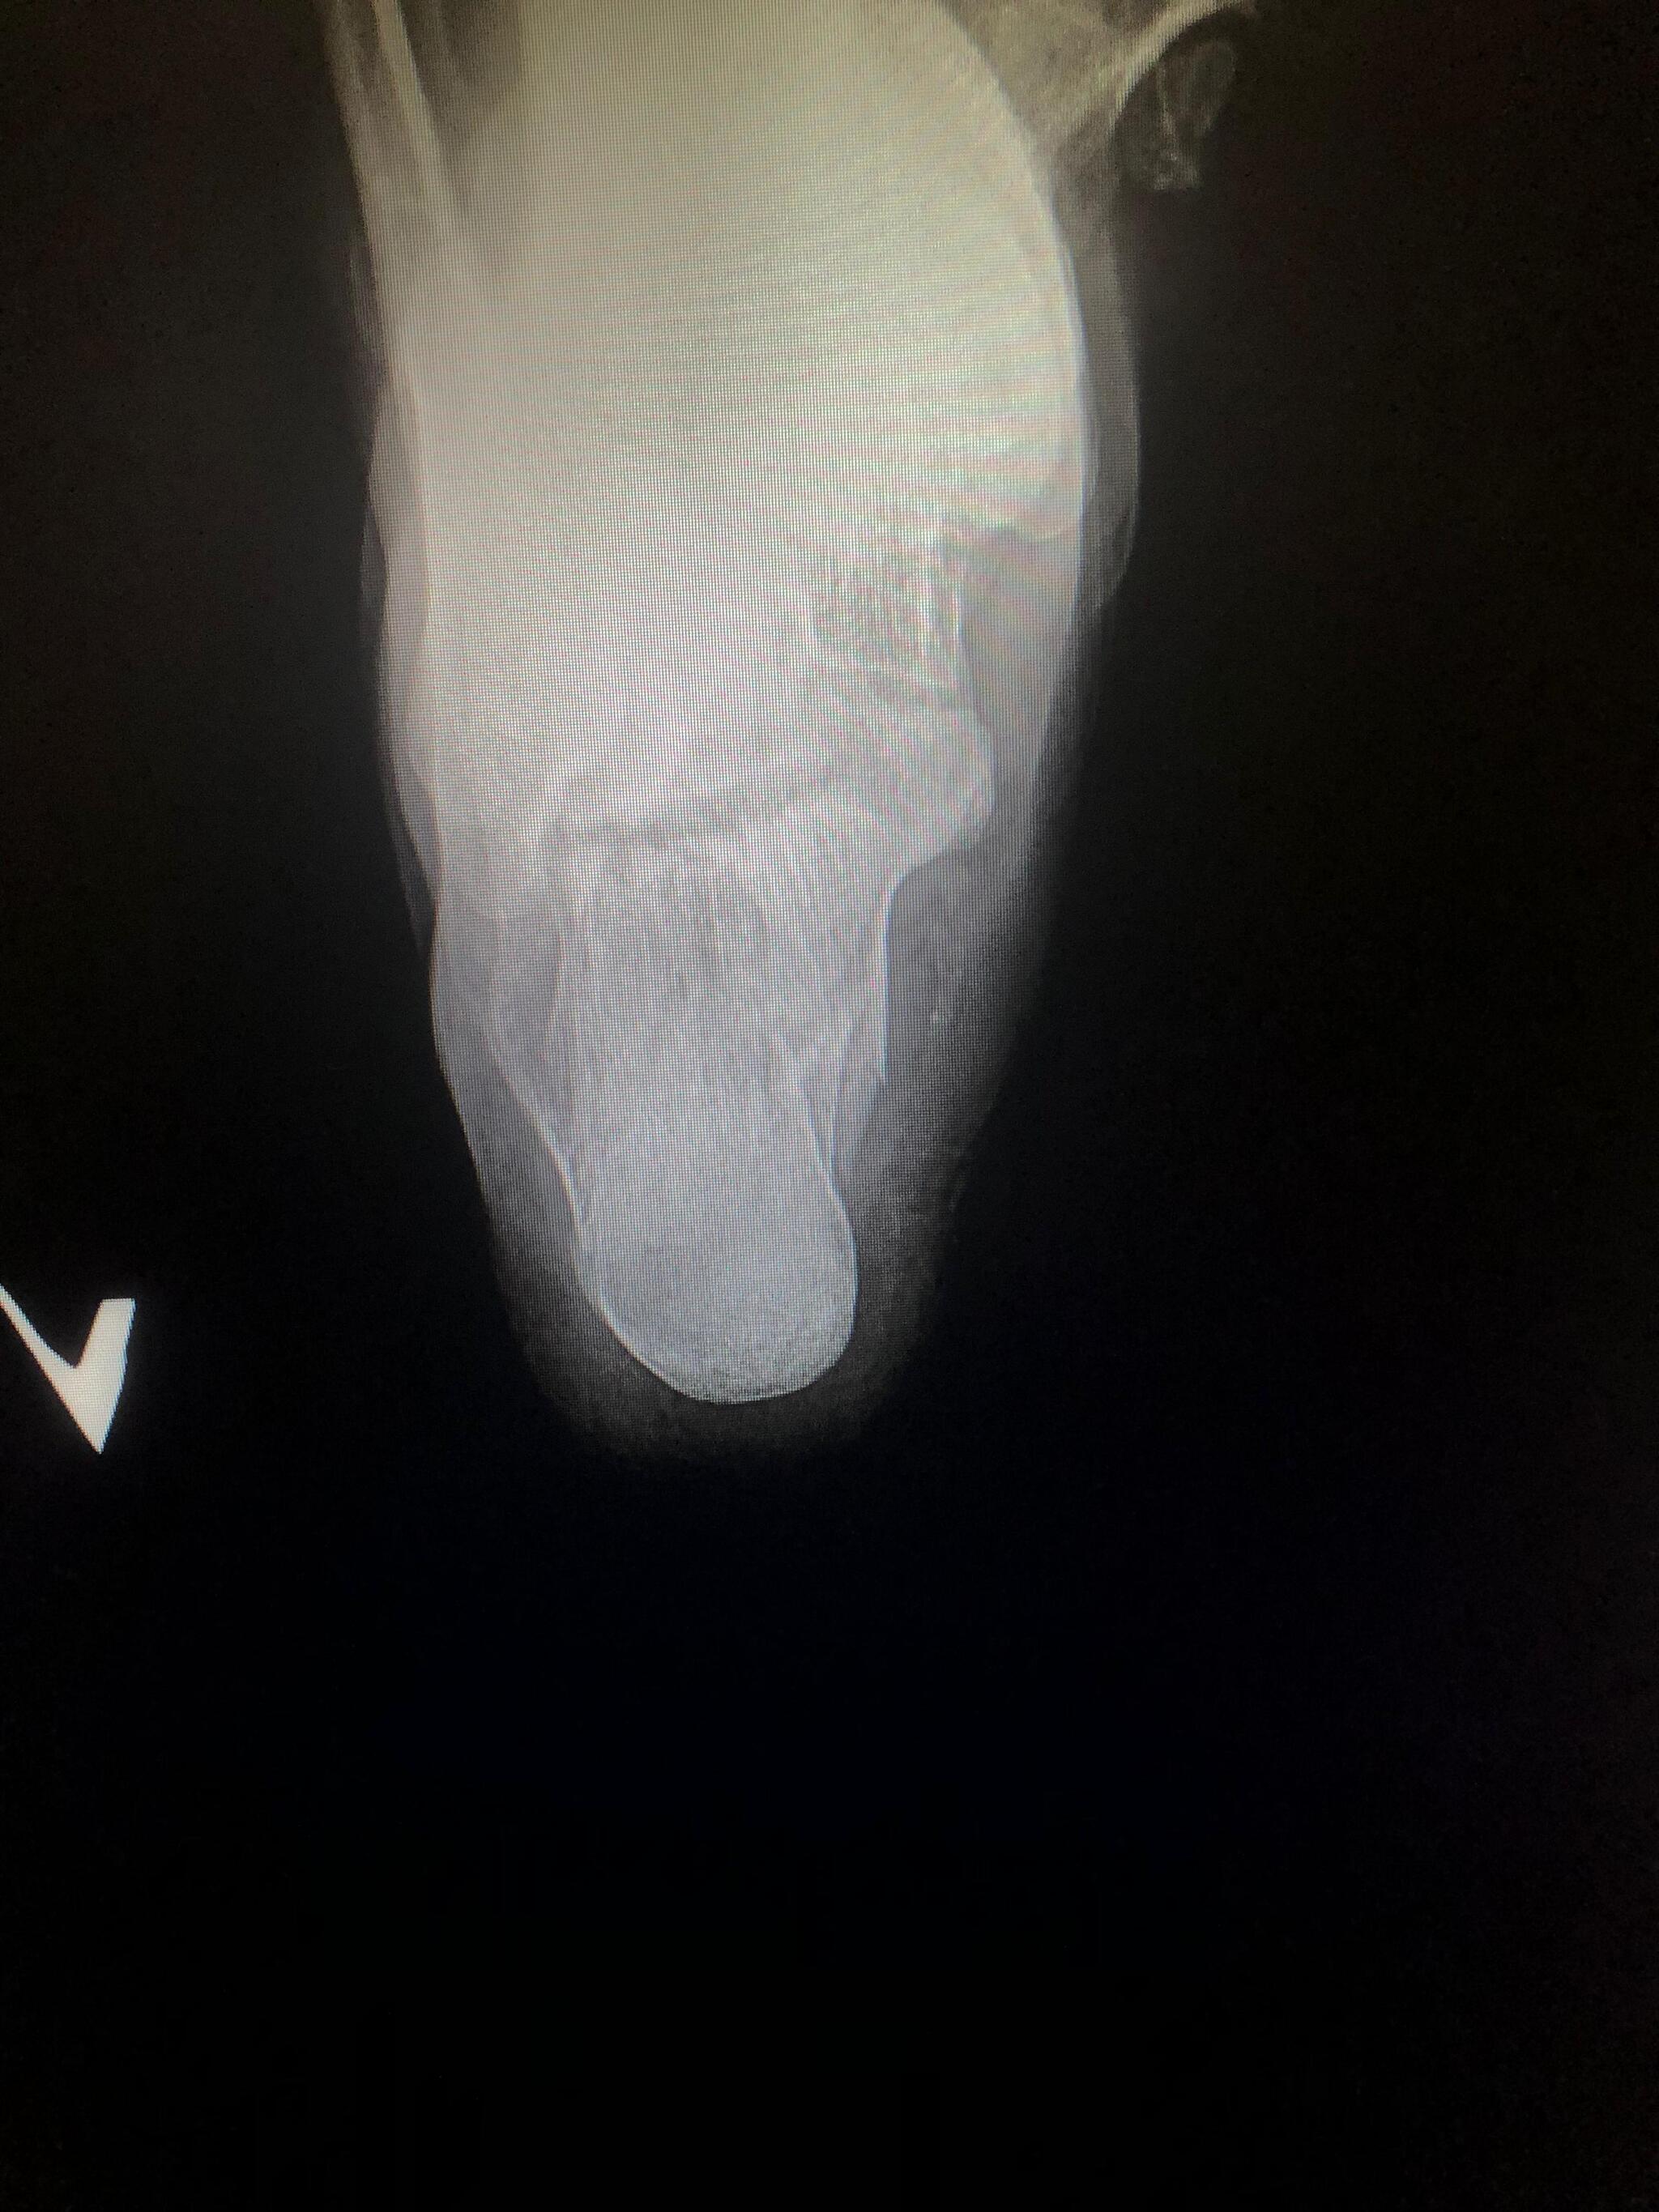

Рентген пятки полезная вещь. И еда для космонавтов нормальная по вкусу. Не такая чтоб каждый день есть, но вполне себе можно перекусить если что.

А насчет рентгена - нельзя же часто его делать, облучение и всё такое